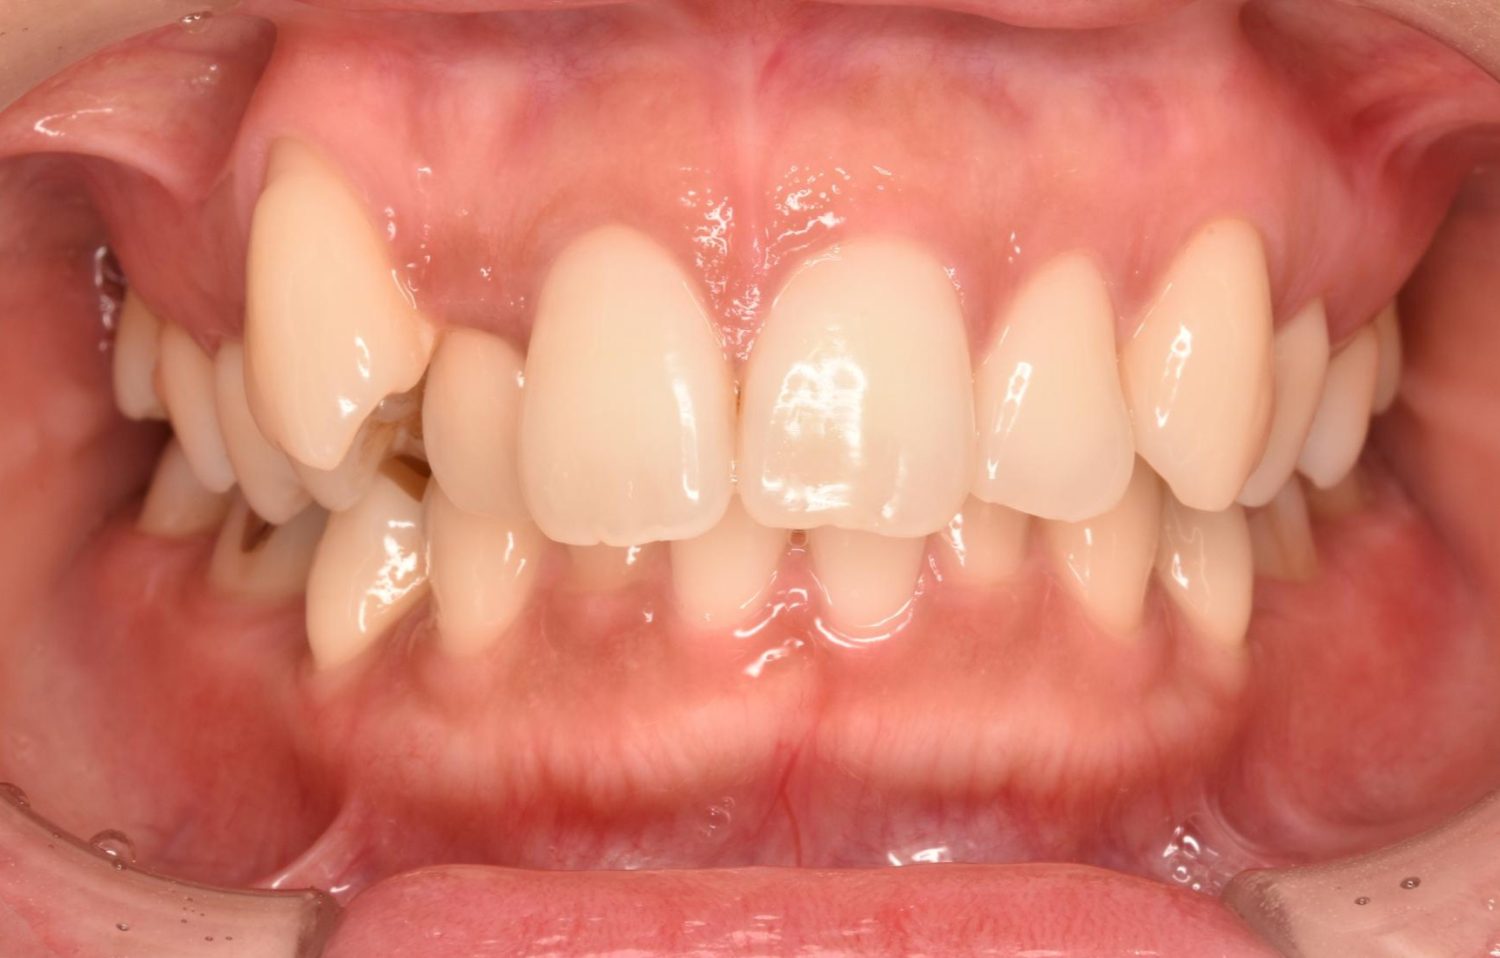

| 主訴 | 20代女性の患者さん。右上の八重歯が突出しており、前歯の見た目にコンプレックスを抱いていた。下顎の左右第2小臼歯(5番)が舌側に大きく傾斜しており、食事の際に、食べかすが詰まりやすく日常的に不快感を覚えていた。噛み合わせの改善と、見た目のバランスを整えたいという希望があり、矯正治療を行うことになった。また、目立ちにくい方法で治療を進めたいという意向から、マウスピース型装置の矯正 “インビザライン”を希望。 |

| 治療内容 | 下顎の左右第2小臼歯(5番)は舌側に大きく傾斜しており、矯正治療における歯の移動効率や全体の歯列バランスを考慮し、便宜抜歯を行った。また、上顎の左右第1小臼歯(4番)についてもスペース確保の目的で抜歯を実施し、全顎的な歯列の配列を円滑に進められるよう計画。矯正装置は、患者さんのなるべく目立ちにくい治療を行いたいという強い希望とライフスタイルに合わせて、マウスピース型矯正装置「インビザライン」(※1)を採用。抜歯が必要となる矯正治療は、診断・治療の難易度が高い方法である。当院ではCTやセファログラムなどの先進的な設備を完備し、多角的な診査診断と豊富な臨床経験をもつ理事長による治療を行うことで、このような難症例にも対応可能。 また、当院は矯正治療だけでなく、むし歯治療やクリーニングなどの一般歯科・予防治療も一貫して管理する包括的な審美治療を行う総合クリニック。治療中にむし歯などの問題が見つかっても、すぐに対応できるため、患者さんの通院の負担をできる限り抑えたスムーズな対応が可能。矯正専門医院ではできない包括的なサポート体制こそが、シャングリラデンタル横浜歯科矯正歯科で矯正治療を受けるメリットである。 矯正治療中は定期検診で経過の確認とクリーニングを行い、必要に応じて治療計画の見直しやマウスピース型装置の追加を行った。患者さんの高い装着遵守率も相まって、歯列は順調に整い、機能的にも審美的にも良好な結果をえることができた。 (※1)未承認医薬品等であるため医薬品副作用被害救済制度の対象とはならない可能性があります。 |